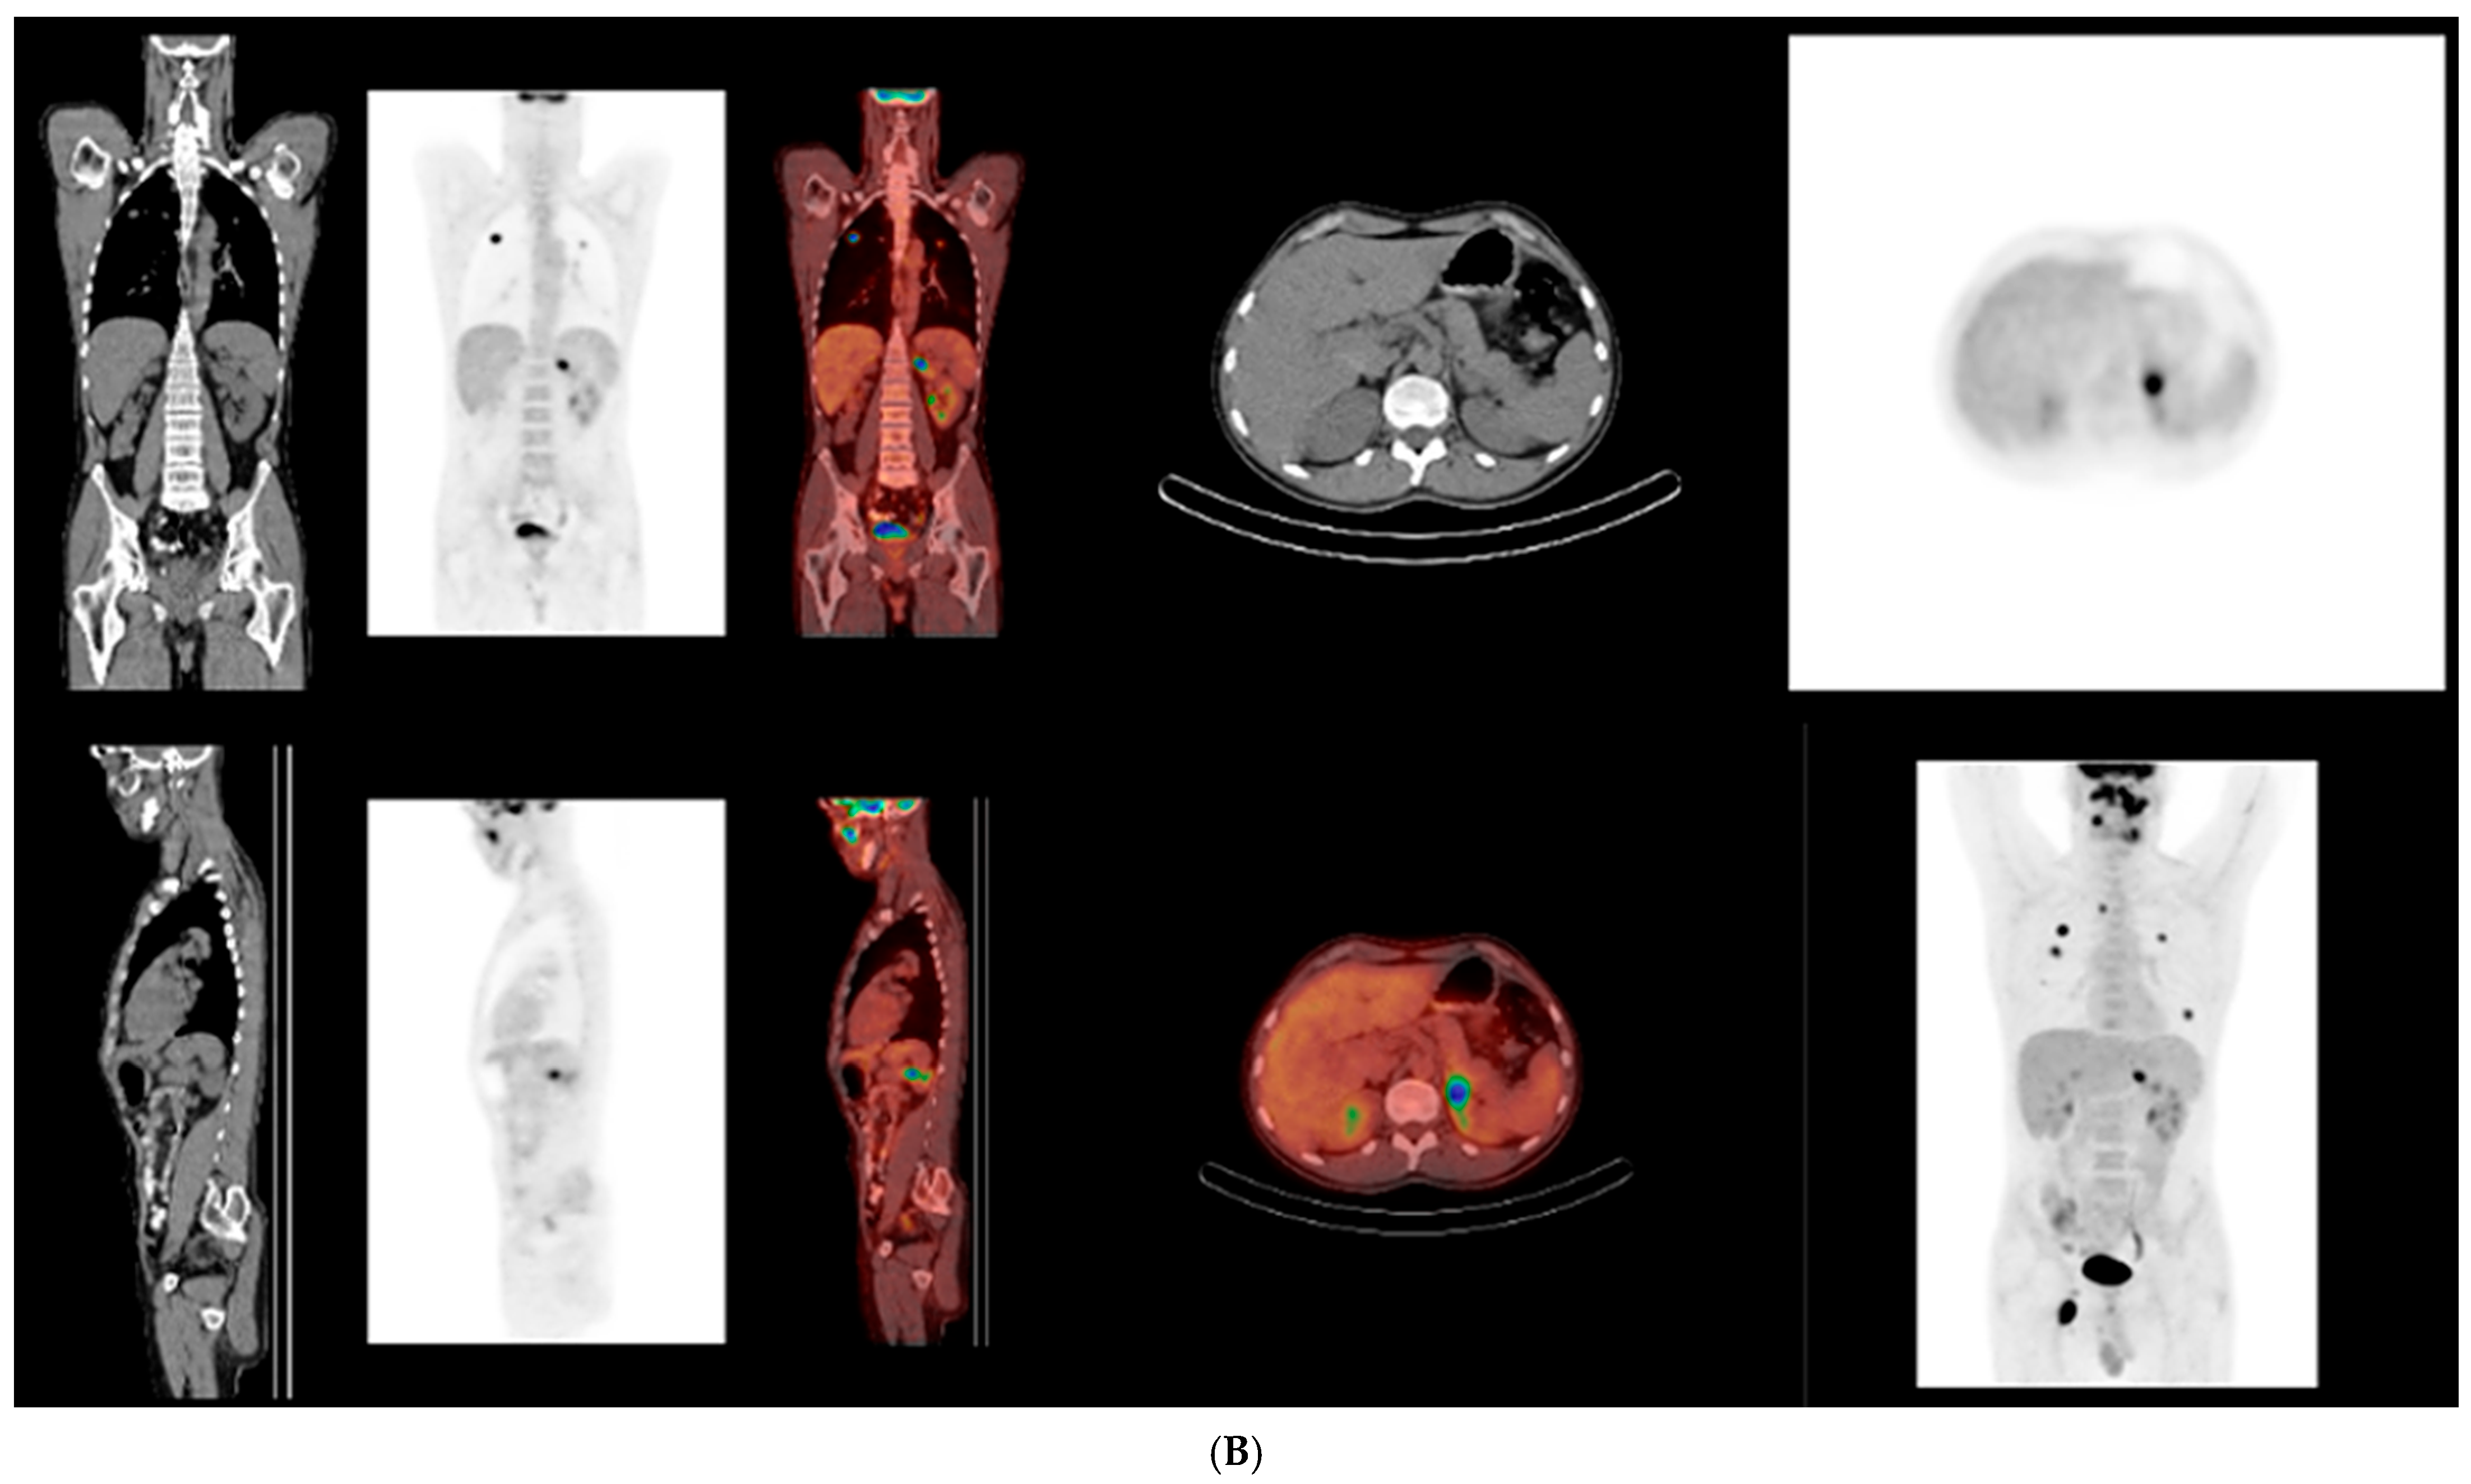

Combined multimodal therapy resulted in a marked initial clinical improvement. During SMILE chemotherapy (weeks 6–10 from initial presentation), significant regression of the oral lesion was observed, accompanied by symptomatic relief (Figure 5 and Figure 6). Following completion of 3D-conformal radiotherapy to a total dose of 50 Gy (month 4), PET-CT demonstrated a partial metabolic and morphological response, consistent with temporary disease control. After a follow-up period of approximately three months (months 5–7) following completion of radiotherapy, the patient remained clinically stable, with no evidence of local progression. However, at approximately nine months from initial presentation, PET-CT revealed extensive systemic relapse, involving nodal, pulmonary, adrenal, cutaneous, and subcutaneous sites (Figure 7).

Figure 7. (A,B) ^18F-FDG PET–CT images obtained at the time of systemic relapse, demonstrating disseminated metabolically active disease involving nodal and extranodal sites.